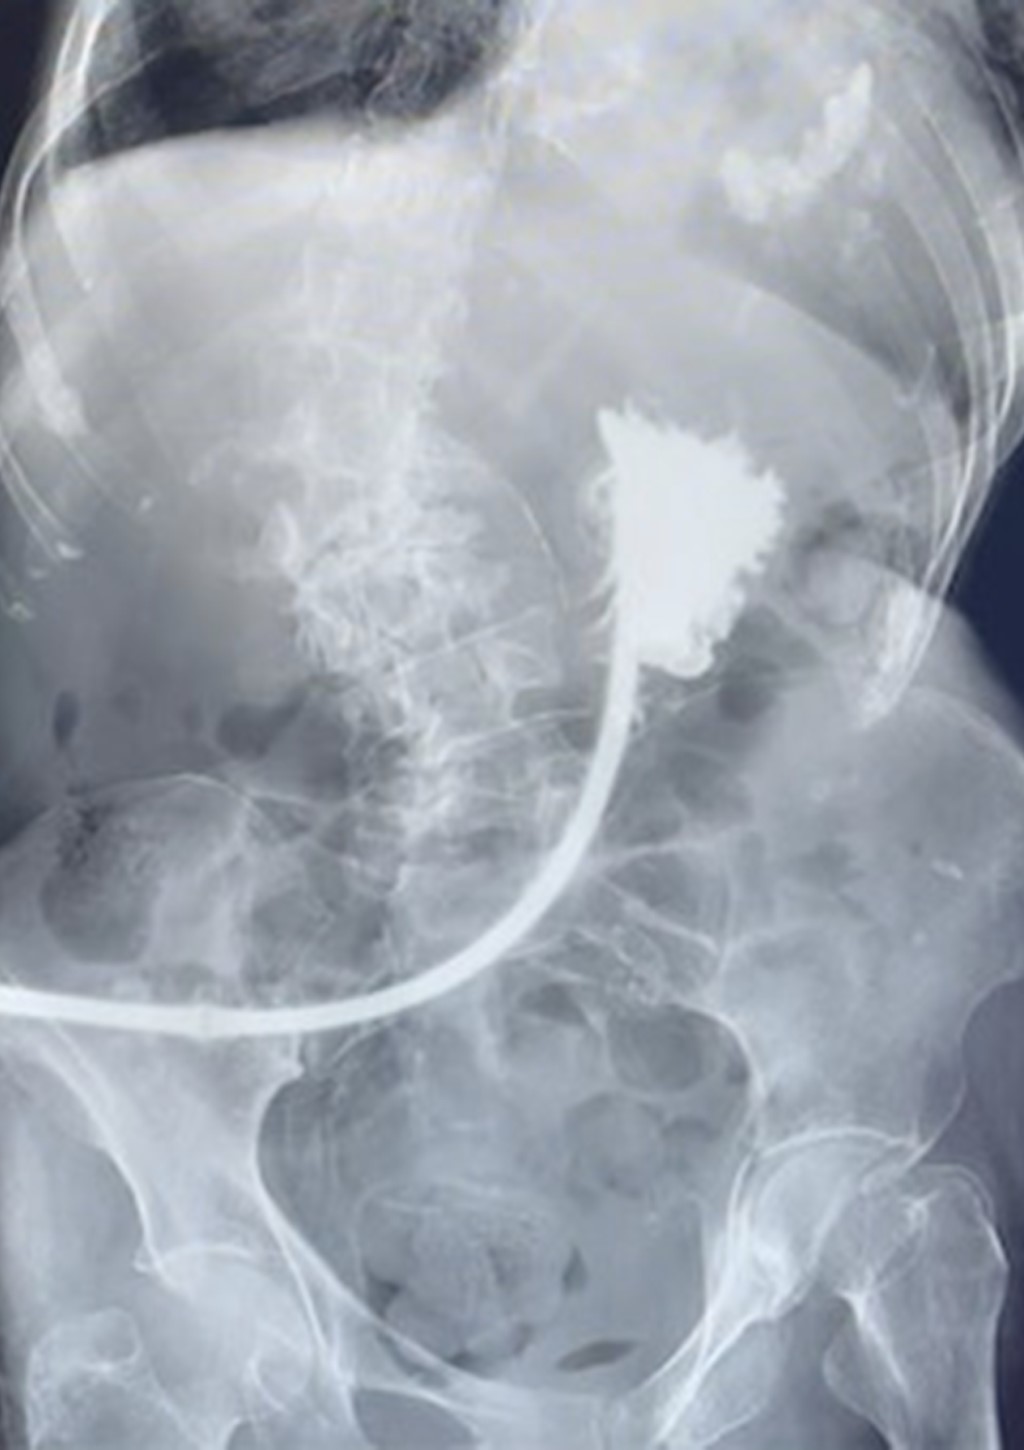

Figure 3